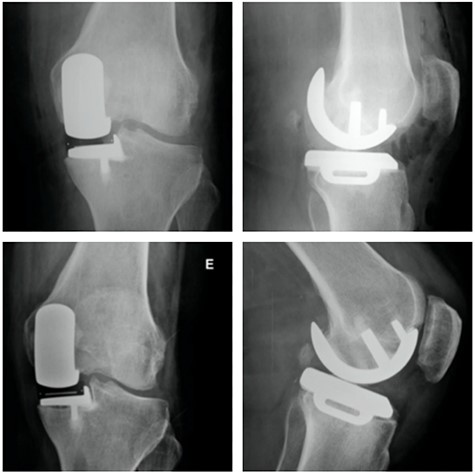

Left knee T2 coronal MRI (top left) showing MP and femoral condyle SIFK with articular failure of both surfaces; Top right: same image (T1); Bottom left: orthostatic anterior view X-ray image of the same patient showing medial compartment bone-on-bone contact; Bottom right: lateral view X-ray image of the same patient.

Top: anterior (left) and lateral view (right) X-ray images of the immediate postoperative period (medial UKA); Bottom: anterior (left) and lateral view (right) X-ray images of the same patient with 5 months of follow-up with tibial component loosening.